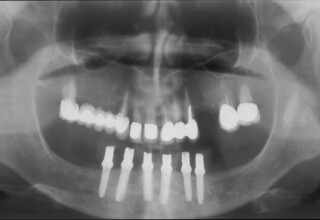

Κάτω γνάθος: εξαγωγές, άμεση τοποθέτηση εμφυτευμάτων και άμεση φόρτιση(την ίδια ημέρα) με προσωρινή γέφυρα

Άνω γνάθος: σταδιακές εξαγωγές, σταδιακή τοποθέτηση εμφυτευμάτων και σταδιακή ενσωμάτωση τους στην προσωρινή γέφυρα ώστε η ασθενής να μην μείνει ούτε μια ημέρα χωρίς αποκατάσταση. Στόχος η συνεχής λειτουργική και αισθητική αποκατάσταση της ασθενούς χωρίς άμεση φόρτιση των εμφυτευμάτων λόγω ανατομικών ιδιαιτεροτήτων.

Χρησιμοποιήθηκαν παλαιές χαμογελαστές φωτογραφίες της ασθενούς γιατί είχε χαθεί τελείως το φυσικό σχήμα των δοντιών εξαιτίας των πολλαπλών προσθετικών προσπαθειών που είχαν γίνει στο παρελθόν. Μεταφέρθηκε στην προσωρινή γέφυρα η σχέση των φυσικών δοντιών μεταξύ τους άλλα και με τα χείλη. Δοκιμάστηκε η φώνηση και η μάσηση με δυο διαφορετικές προσωρινές άνω γέφυρες και εκτιμήθηκε η αισθητική απόδοση τους. Αφού επιτεύχθηκαν σε βαθμό ικανοποιητικό η φώνηση και η αισθητική εμφάνιση της οδοντοφυΐας, η προσωρινή αποκατάσταση χρησιμοποιήθηκε ως οδηγός για την τελική.